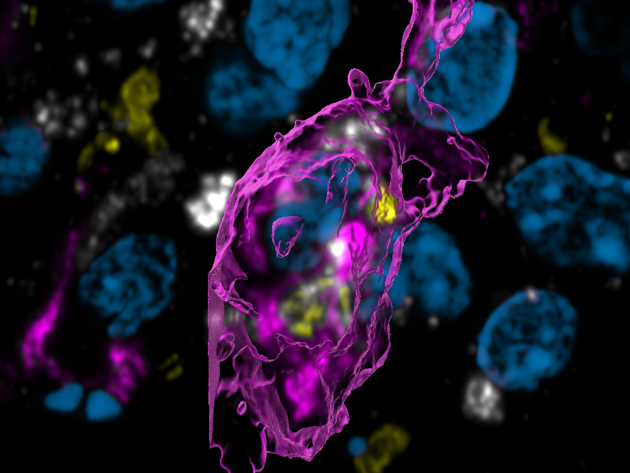

Figuur A - vet-geladen macrofaag in glioblastoom die myeline opneemt

Figuur A

Een vet-geladen macrofaag in een glioblastoom (paars) in een muis die myeline opneemt (geel).

Na de opname van de myeline worden de vetten hergebruikt en bewaard in vet druppels (wit).